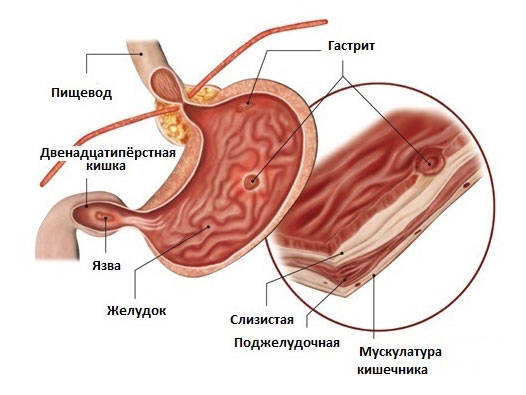

Гастрит — заболевание желудка, которое сопровождается острым или хроническим воспалением слизистой оболочки органа. Гастрит является одной из наиболее распространенных патологий пищеварительной системы. Среди заболеваний желудка она составляет 80%. Риск возникновения гастрита повышается с возрастом. По статистике, этой патологией болеет 70-90% пожилых людей. В последние годы участились случаи диагностики заболевания у детей 8-13 лет.

При отсутствии адекватного лечения гастрит неблагоприятно влияет на качество жизни пациента. Ухудшается переваривание пищи и усвоение питательных веществ, что сказывается на общем состоянии организма, работоспособности и активности пациента. В тяжелых случаях возможно развитие осложнений (язвенной болезни, профузного кровотечения, рубцовых деформаций, свищей, мегалобластной анемии, кахексии). Метаплазия эпителия чревата формированием злокачественной опухоли (аденокарцинома желудка).

Гастрит развивается в результате воздействия сразу нескольких повреждающих факторов. К таковым относят ишемию тканей, нарушения моторной и секреторной функций желудка, контакт слизистых с агрессивными веществами. Спровоцировать активное воспаление слизистого слоя способны следующие факторы: